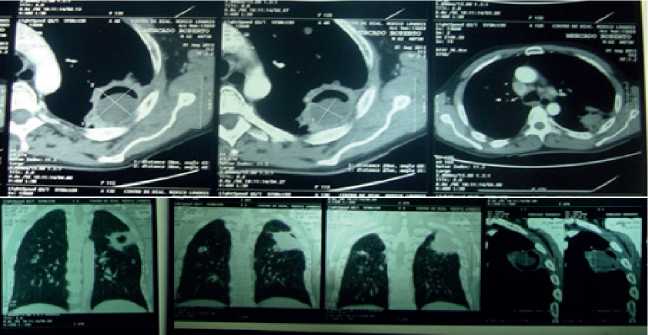

Se solicito tomografía axial computarizada (TAC) que evidencia lesión intracavitada en región postero-lateral del lóbulo superior izquierdo (Figura 2) lo que sugiere no descartar que se trate de aspergiloma y/o micetoma intra-cavitario, asociados a discretos cambios de atelectasia supra e infrayacente. Presencia de otras lesiones cavitadas en lóbulo superior derecho y lóbulo medio ipsilateral, asociado a escasos cambios de patrón de fibrosis y pequeña zona de atelectasia en región anterior del lóbulo medio ipsilateral.

Figura 2. TACSe evidencia en región posterolateral del lóbulo superior izquierdo lesión intracavitada no descartándose tratarse de aspergiloma y/o micetoma intracavitario, asociados a discretos cambios de atelectasia supra e infrayacente. Presencia de otras lesiones cavitadas en lóbulo superior derecho y lóbulo medio ipsilateral, asociado a escasos cambios de patrón de fibrosis y pequeña zona de atelectasia en región anterior del lóbulo medio ipsilateral.